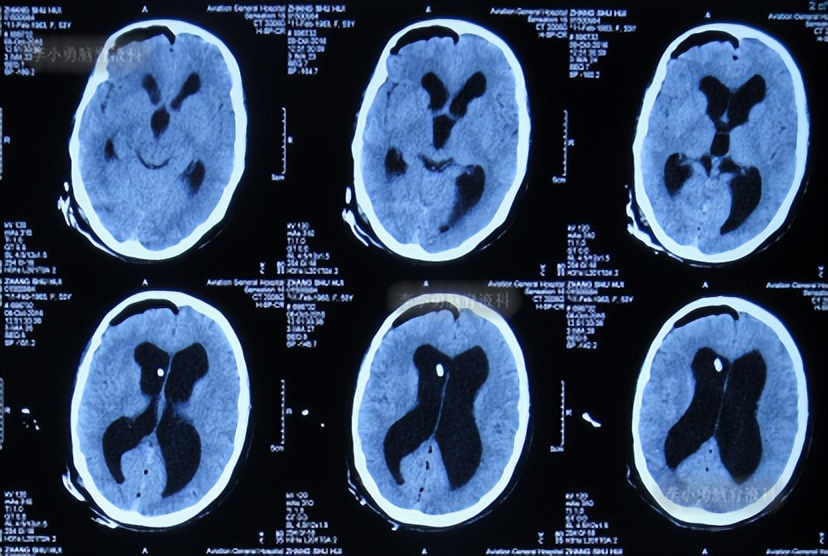

患者2014年6月20日出现持续头晕的症状,不能自行缓解,于2014年6月24日和6月26日分别就诊于甘肃省平凉县某医院和陕西省西安某医院,进行了头颅MRI和头颅CT示脑室扩张,脑积水( 图-1 、 图-2 )。

图-2: 2014年6月26日头颅CT

为治疗脑积水,于头晕发病8天后即2014年6月28日,就诊于陕西省西安某三甲医院神经外科,当天查头颅MRI:脑积水( 图-3 )。

图-3: 2014年6月28日头颅MRI

住院后第5天即2014年7月2日,进行了脑室腹腔分流术,术后次日即2014年7月3日查头颅CT:脑室分流术后状态( 图-4 )。

图-4: 2014年7月3日头颅CT

脑室腹腔分流术后第7天即2014年7月7日,查头颅CT:脑室仍然扩张( 图-5 )。

图-5: 2014年7月7日头颅CT